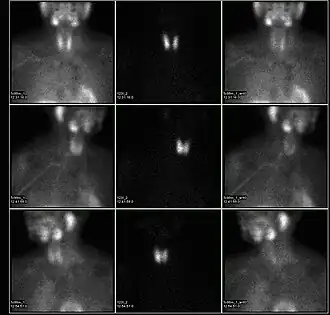

![]() A nuclear medicine parathyroid scan demonstrates a parathyroid adenoma adjacent to the left inferior pole of the thyroid gland. The above study was performed with Technetium-Sestamibi (1st column) and Iodine-123 (2nd column) simultaneous imaging and the subtraction technique (3rd column). | |

A sestamibi parathyroid scan is a procedure in nuclear medicine which is performed to localize parathyroid adenoma, which causes Hyperparathyroidism.[1] Adequate localization of parathyroid adenoma allows the surgeon to use a minimally invasive surgical approach.